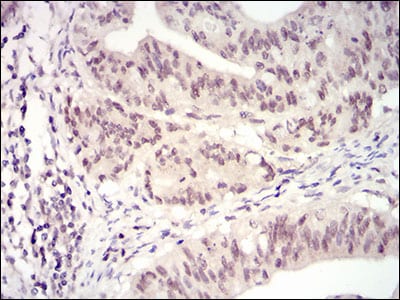

- Immunohistochemical analysis of paraffin-embedded human rectum cancer tissues using CDK4 mouse mAb with DAB staining.